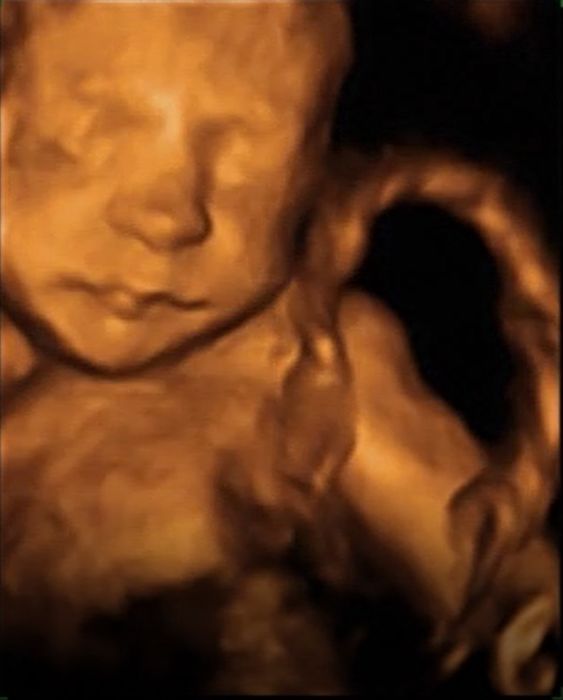

My byli na 4D na zacatku ledna v 25tt a byli jsme nadseni, doktor taky rikal, ze je pekne videt :) Mame video 4D a pak komentovane video 2D. Bude to krasna pamatka.